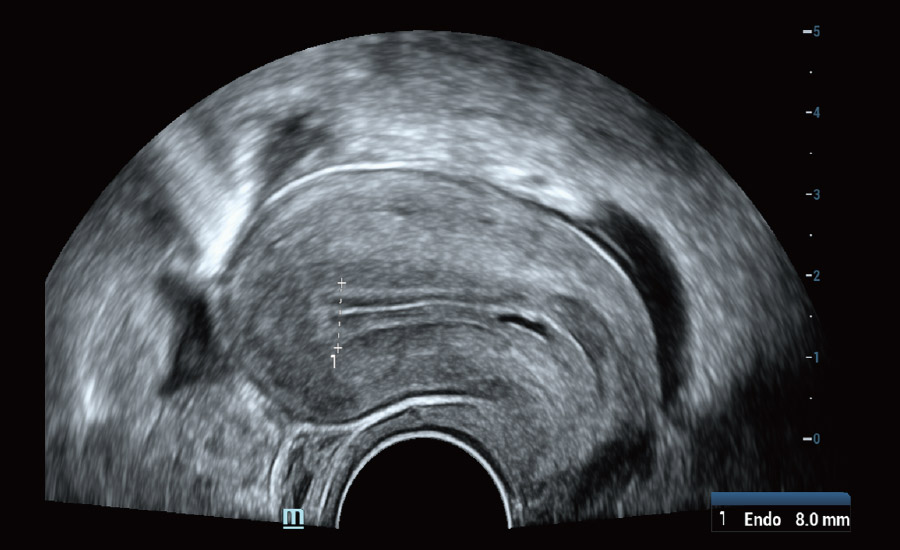

UMA (Ultra-Micro Angiography)

The innovative technology breaks the bottlenecks of traditional Doppler imaging. With ultra-high spatial resolution and flow sensitivity, it allows detecting super-subtle and super-slow flow perfusions, thereby extending the clinical application of qualitative and quantitative ultrasound evaluation in fetal brain, kidney, placenta, endometrium, ovary, etc.

UMA - uterine and endometrial flow

Scenario-oriented Full-stack Intelligence

Combining advanced algorithms and domain-specific knowledge, the innovative Smart Scene solution enables auto identification of tissue characteristics and provides organ-specific diagnosis with full-stack intelligence. Based on auto scenario identification, the solution not only realizes smart 2D scanning with auto settings and measurements, but also delivers 3D full-stack intelligence in every step from volume imaging optimization to the difficult 2D plane acquisition, and quantification throughout whole procedure. It helps a lot in reducing the dependency on clinical skills, while increasing diagnostic accuracy, confidence and efficiency.

Gynecology